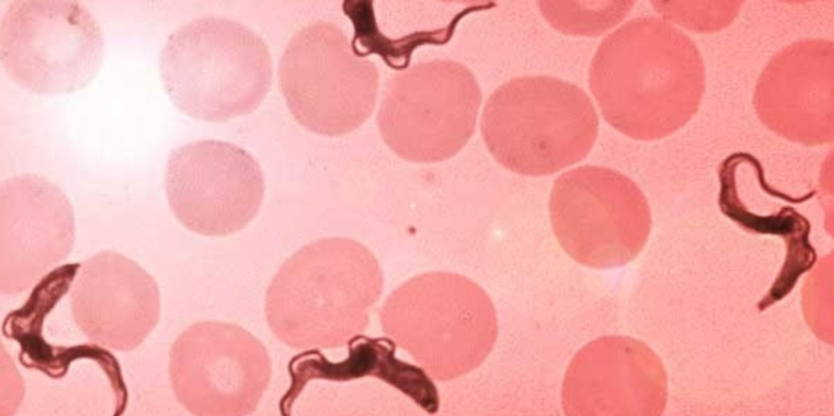

Trypanosoma spp.

Trypanosoma spp.